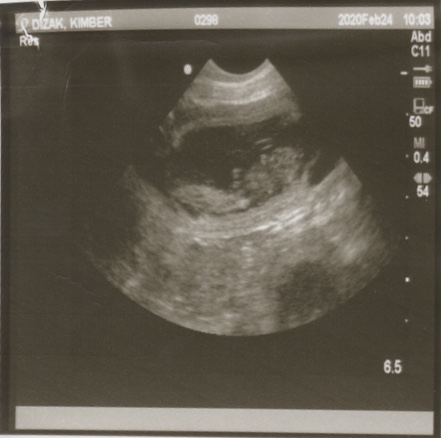

2-24-20

Pregnancy Confirmed

Today we went for an ultrasound to see if Kimber was as pregnant as she looks…and the answer is YES! The doctor was thrilled with how she is progressing and says that she should have happy and healthy babies.